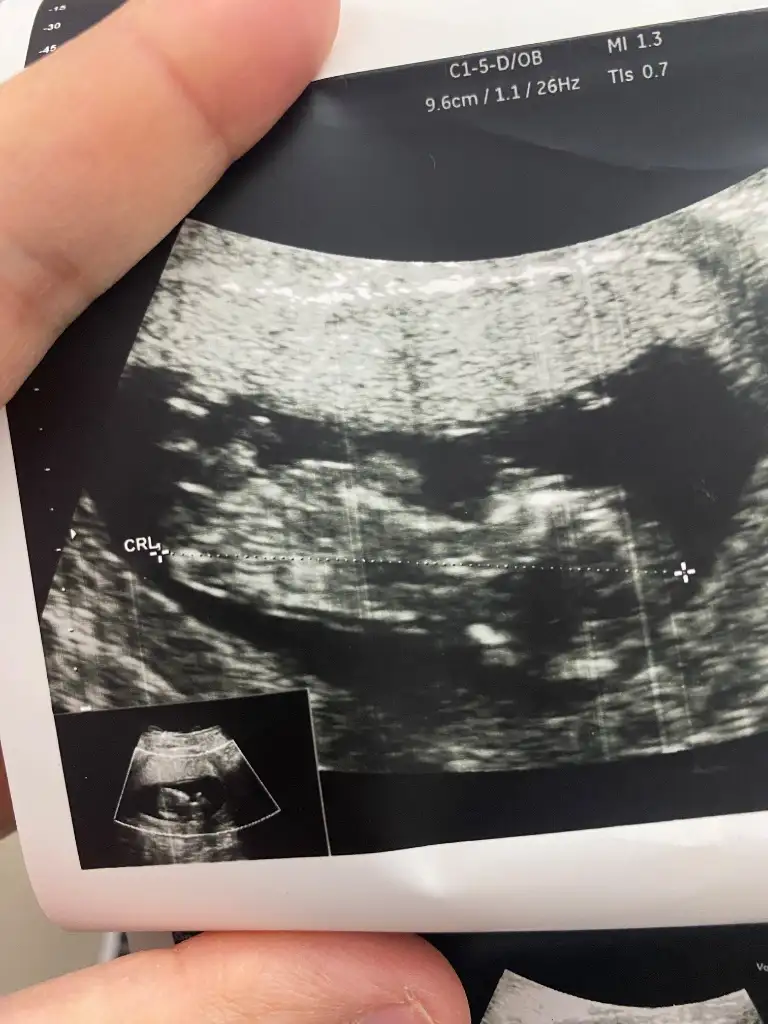

Erkek hissettimKızlar 10 haftalık hamileyim cinsiyet tahmini sizce nedir

Başka foto var mı iki bacak arası gibi bu ama bulanık çıkmış gördüğüm çıkıntıysa erkek ama emin olamadımBunada bakar mısınız

Bunlar var canimBaşka foto var mı iki bacak arası gibi bu ama bulanık çıkmış gördüğüm çıkıntıysa erkek ama emin olamadım

Başka foto var mı iki bacak arası gibi bu ama bulanık çıkmış gördüğüm çıkıntıysa erkek ama emin olamadım

Kızlar tahmininiz nedir

Fotolar doktor taarafından hiç güzel çekilmmemişKızlar tahmininiz nedir